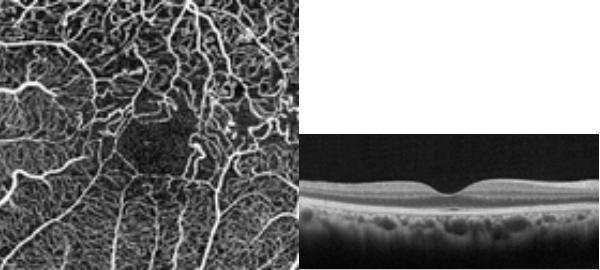

●OCT(光干渉断層計)

光干渉の原理を用いて網膜の断層像を測定する装置です。網膜の各層の形態を詳しく見る事ができる為、網膜の浮腫・剥離・出血等の範囲を観察する事ができ、網膜疾患の評価に非常に有用な機械です。また網膜疾患だけではなく早期の緑内障の発見や、進行の評価を他覚的に捉える事もできます。更に造影剤を用いないで眼底の血流機能を観察する機能(OCT Angiography)も有している為、造影剤が使用できない患者様への眼底血流検査も可能となります。